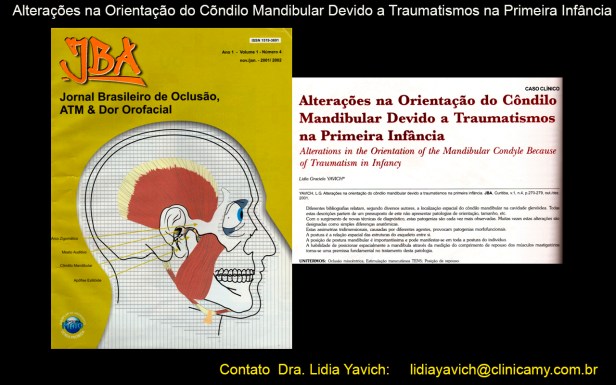

Pode-se observar nesta imagem a alteração do eixo de crescimento do côndilo mandibular. Alterações na Orientação do Côndilo Mandibular Devido a Traumatismos na Primeira Infância

Caso clínico apresentado na edição número 4 do Jornal Brasileiro de Oclusão, ATM e Dor Orofacial, de outubro/dezembro de 2001.

Artigo publicado no Journal of Cranio-Maxillary Diseases, volume 3, issue 2, julho/dezembro de 2014.

Alterações na Orientação do Côndilo Mandibular Devido a Traumatismos na Primeira Infância

Caso clínico apresentado na edição número 4 do Jornal Brasileiro de Oclusão, ATM e Dor Orofacial, de outubro/dezembro de 2001.

Artigo publicado no Journal of Cranio-Maxillary Diseases, volume 3, issue 2, julho/dezembro de 2014.